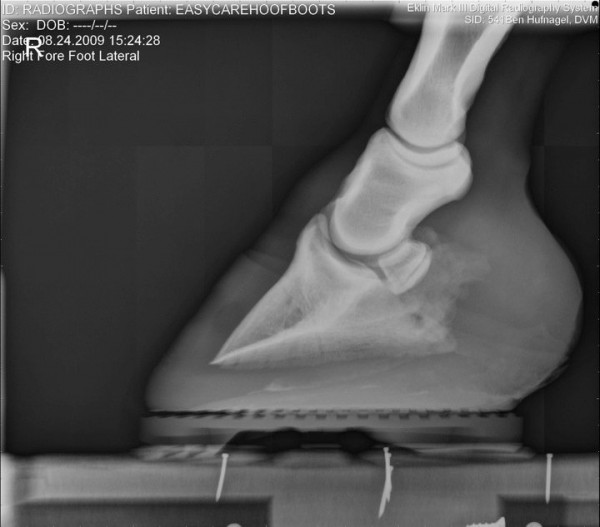

Společnost EasyCare si dělá vlastní průzkumy-výzkumy… zde jsou zajímavé fotografie jak to vypadá když je kopýtko v botě, zůstává ve svém přirozeném tvaru, kopytní mechanismus je neomezený a kůň ho má možnost plně přirozeně využívat 🙂